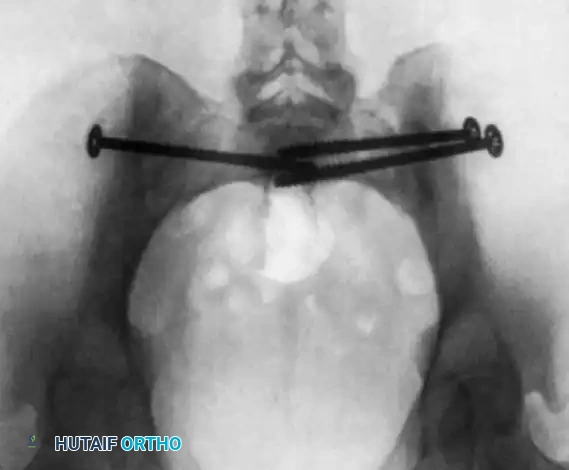

Image

Postoperative CT scan showing a catastrophic "in-out-in" error. The cephalad anterior iliosacral screw on the patient’s left side is extraosseous, resulting in a severe left L5 nerve root injury.

Surgical Warning: Never advance a drill or screw if the guide wire trajectory cannot be definitively confirmed in the Inlet, Outlet, AND True Lateral planes. If visualization is obscured by bowel gas or obesity, the procedure must be converted to an open approach or alternative fixation (e.g., posterior tension band plating) must be utilized.